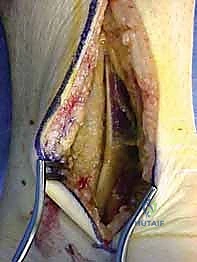

المرحلة الثانية: النهج الجراحي (الشقوق الجراحية)

نظراً لتعقيد عظم الكاحل، غالباً ما يتطلب الأمر شقين جراحيين (Dual Approaches) للوصول إلى العظم من زوايا مختلفة دون تدمير الأنسجة السليمة:

* النهج الأمامي الإنسي (Anteromedial Approach): شق يتم إجراؤه على الجانب الداخلي للكاحل، بين وتر العضلة الظنبوبية الأمامية والكعب الإنسي. يتيح هذا الشق رؤية ممتازة لعنق الكاحل والجانب الداخلي لجسم العظم. في بعض الحالات المعقدة، قد يضطر الدكتور هطيف لإجراء "قطع عظمي للكعب الإنسي" (Medial Malleolar Osteotomy) للوصول إلى عمق المفصل، ثم إعادة تثبيته لاحقاً.

* النهج الأمامي الجانبي (Anterolateral Approach): شق يتم إجراؤه على الجانب الخارجي، يتيح رؤية النتوء الجانبي، المفصل تحت الكاحلي، والجانب الخارجي للعنق والجسم.